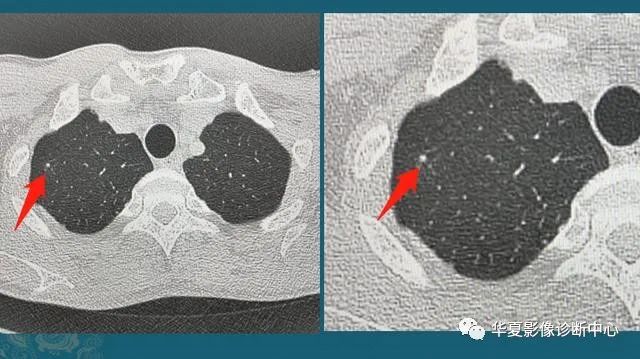

图5还有一种,随访过程中逐渐增大的肺结节,不论磨玻璃还是实性结节,都要重视!绝大多数早期肺癌生长缓慢,对无法定性的肺结节,定期复查是个很实用的办法,可以避免过度医疗,也防止漏诊。豪大夫每年都能发现很多从肺小结节长大的肺癌,挑出两个速度最快的分享一下:

图6这位病人2016年体检还是正常的,2017年查出一个3 mm的肺结节,用了两年半时间,增长到>1 cm,手术病理是肺腺癌。注意:这几乎是最快的一类的,很少见!所以高危人群推荐每年胸部体检一次是有益的。

图7这是一位老年男性,有吸烟史,也是在两年多的时间内,肺结节从不足3 mm长到1 cm以上,后来病理确诊肺鳞癌。中老年人定期胸部CT体检,可以及时发现这些生长较快的恶性肺结节,予以手术根治。就像毒草一样,及时发现连根拔掉,就不会泛滥。最后给大家看几个手术成功的肺结节,有个直径超过3 cm,已经属于肿块了(红箭头是肿瘤,蓝箭头是手术瘢痕):